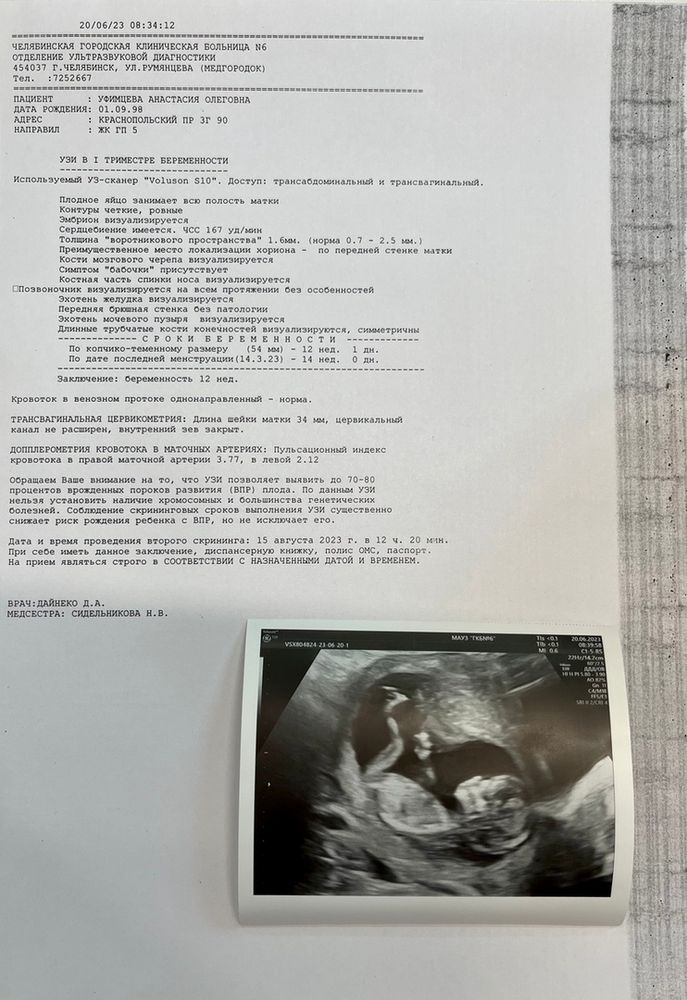

УЗИ, КТГ, доплерСкрининг проходила по омс, но в этом роддоме тот же аппарат узи, на котором все платные приемы я проходила + восхитительные врачи в отделении + скрининг делает сам зав. отделением, поэтому в целом и приняла решение "не переплачивать". Проблема в том, что полноценный результат будет у уч. гинеколога аж через 2 недели, а на прием попаду еще через несколько дней после этого. Сейчас на руках у меня только результат узи, и чем дольше я на него смотрю - тем больше вопросов и переживаний.

Ну то есть в целом вроде все хорошо... И сам врач тоже сказал, что по узи все в порядке и волноваться не о чем.

Но почему-то нет ни слова про воды... Вообще как будто очень мало информации в сравнении с результатами у других...

Плюс ПИ, я в прошлом посте уже писала, в итоге нагуглила, что в одной из артерий нормально, а в другой серьезное превышение. Ну и еще всякого нагуглила. С каждым днем все сложней не переживать.